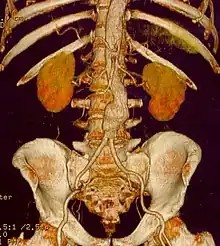

Abdominal aortic aneurysm

Abdominal aortic aneurysms (AAAs) are more common than their thoracic counterpart. One reason for this is that elastin, the principal load-bearing protein present in the wall of the aorta, is reduced in the abdominal aorta as compared to the thoracic aorta. Another is that the abdominal aorta does not possess vasa vasorum, the nutrient-supplying blood vessels within the wall of the aorta. Most AAA are true aneurysms that involve all three layers (tunica intima, tunica media and tunica adventitia). The prevalence of AAAs increases with age, with an average age of 65–70 at the time of diagnosis. AAAs have been attributed to atherosclerosis, though other factors are involved in their formation.[7]

The risk of rupture of an AAA is related to its diameter; once the aneurysm reaches about 5 cm, the yearly risk of rupture may exceed the risks of surgical repair for an average-risk patient. Rupture risk is also related to shape; so-called "fusiform" (long) aneurysms are considered less rupture-prone than "saccular" (shorter, bulbous) aneurysms, the latter having more wall tension in a particular location in the aneurysm wall.[9]

Before rupture, an AAA may present as a large, pulsatile mass above the umbilicus. A bruit may be heard from the turbulent flow in the aneurysm. Rupture may be the first sign of AAA. Once an aneurysm has ruptured, it presents with classic symptoms of abdominal pain which is severe, constant, and radiating to the back.[9]

The diagnosis of an abdominal aortic aneurysm can be confirmed by the use of ultrasound. Rupture may be indicated by the presence of free fluid in the abdomen. A contrast-enhanced abdominal CT scan is the best test to diagnose an AAA and guide treatment options.[10]